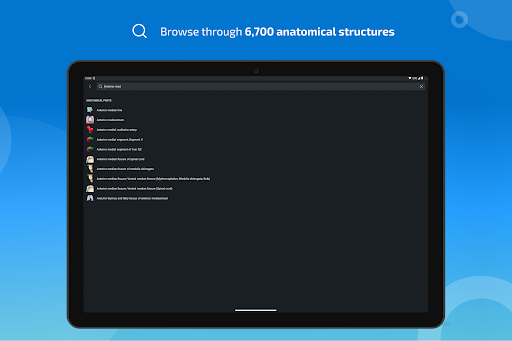

*Find your anatomical parts more easily thanks to the new, more intuitive and powerful search feature